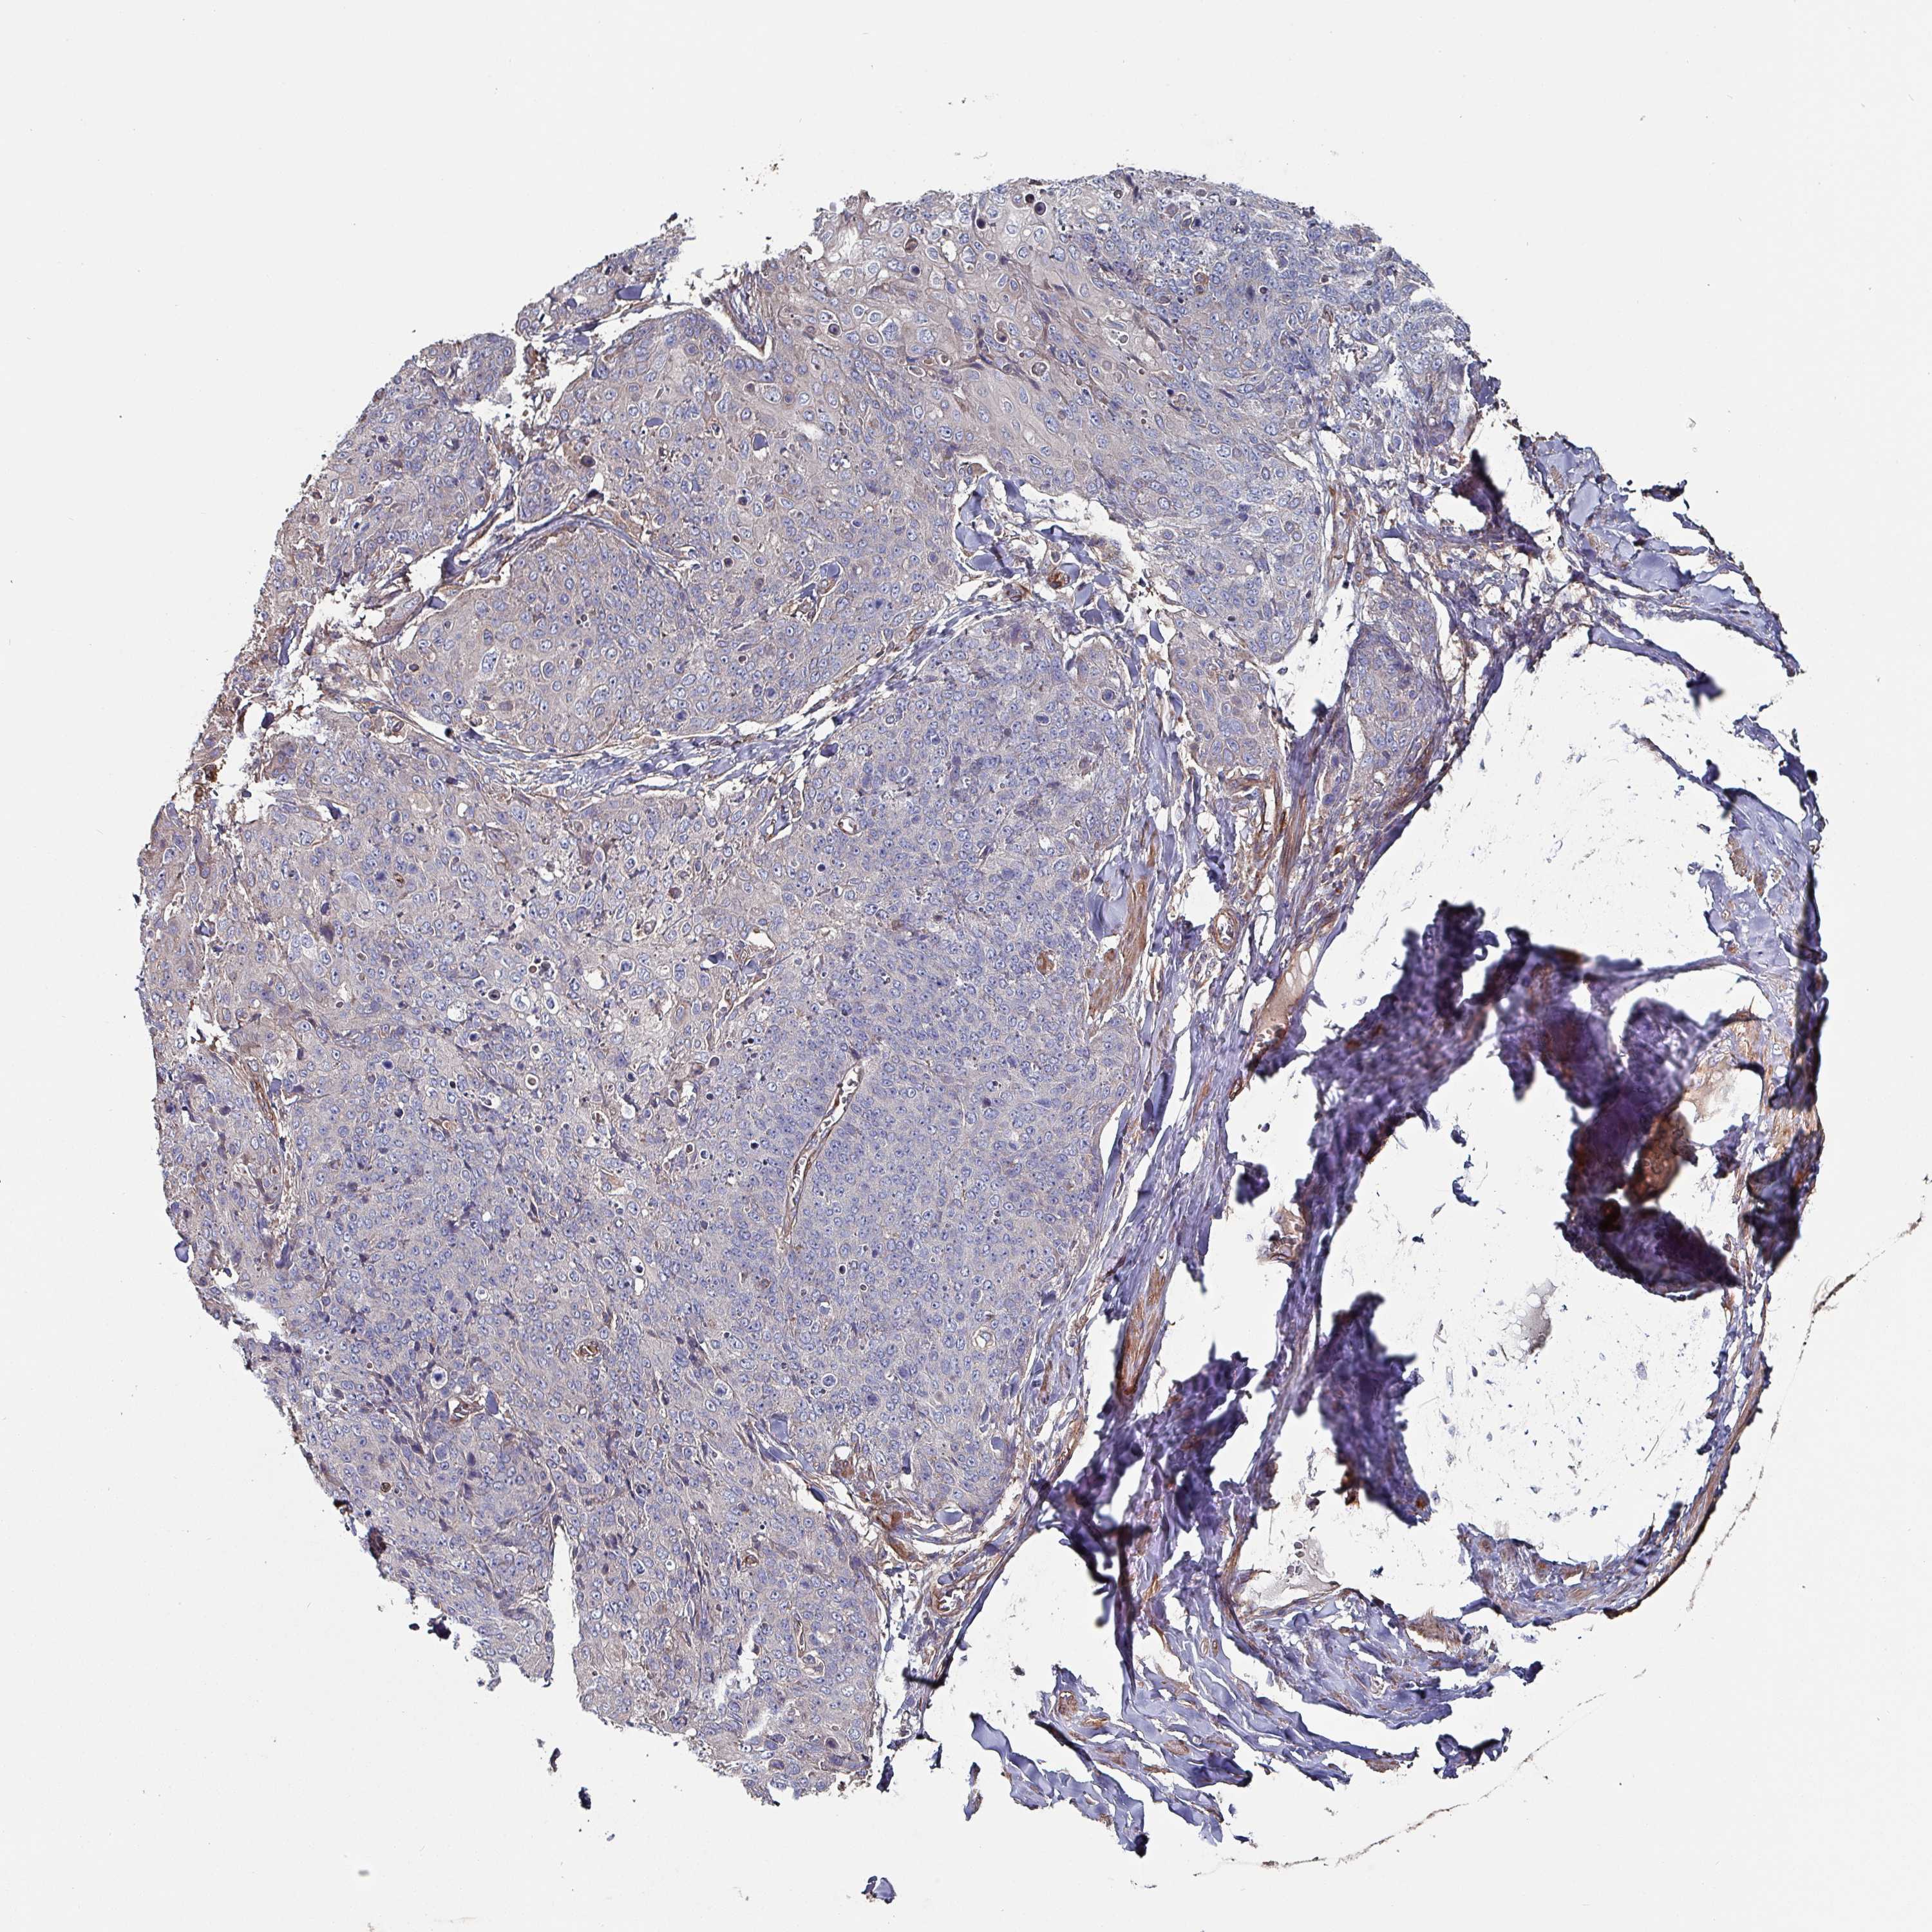

Basal cell and squamous cell cancer

SKIN CANCER - Protein expressioni

A mouse-over function shows sample information and annotation data. Click on an image to view it in a full screen mode. Samples can be filtered based on level of antibody staining by selecting one or several of the following categories: high, medium, low and not detected. The assay and annotation is described here.

Antibody stainingi

Antibody staining in the annotated cell types in the current human tissue is reported as not detected, low, medium, or high, based on conventional immunohistochemistry profiling in selected tissues. This score is based on the combination of the staining intensity and fraction of stained cells.

Each image is clickable and will lead to virtual microscopy that enables deeper exploration of all samples and also displays staining intensity scores, fraction scores and subcellular localization as well as patient and tissue information for each sample.

Antibody HPA051569

Staining

High

Medium

Low

Not detected

Intensity

Strong

Moderate

Weak

Negative

Quantity

>75%

75%-25%

<25%

None

Location

Nuclear

Cytoplasmic/membranous

Cytoplasmic/membranous,nuclear

Squamous cell carcinoma, NOS